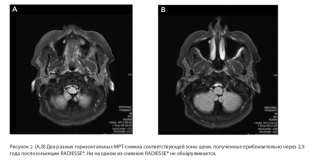

Thus, one of their studies was concerned with the guarantees of the biodegradation of the drug. 2.5 years after the injection of Radiesse to the patient, the injection site was examined using MRI in order to increase the volume of the malar area. The images did not reveal the presence of the drug, which indicates its complete biodegradation. At the same time, the aesthetic result of its introduction was preserved – the soft tissues of the face retained the volume characteristic of a young age, although the patient was 50 years old at the time of the filler injection.